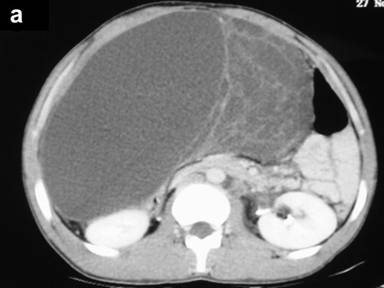

Clinical examination revealed abdominal swelling with generalized tenderness occupying the whole abdomen and almost reaching up to the pelvis. Blood investigation revealed polymorphonuclear leukocytosis (total leukocyte count 12,600 mm-3, reference range: 4,000-11,000 mm-3; polymorphs 91%, reference range: 40-75%). The serum amylase level was 297 U/L (reference range: 20-85 U/L). Liver function tests and CA 19-9 levels were normal. An ultrasound carried out outside our hospital found a large septate cystic collection in front of the pancreas and reported as acute pancreatitis with fluid collection. A CT scan revealed a large multiseptate cystic lesion (23.2x11.7x26.2 cm) anterior to the pancreas reaching up to the pelvis and displacing the gut loops behind and downwards (Figures 1 and 2). We decided to perform a laparotomy with a presumptive diagnosis of cystic neoplasm of the pancreas.

Figure 1. CECT axial scans showing a multiseptate cystic tumor anterior to the pancreas and reaching up to the pelvis. |